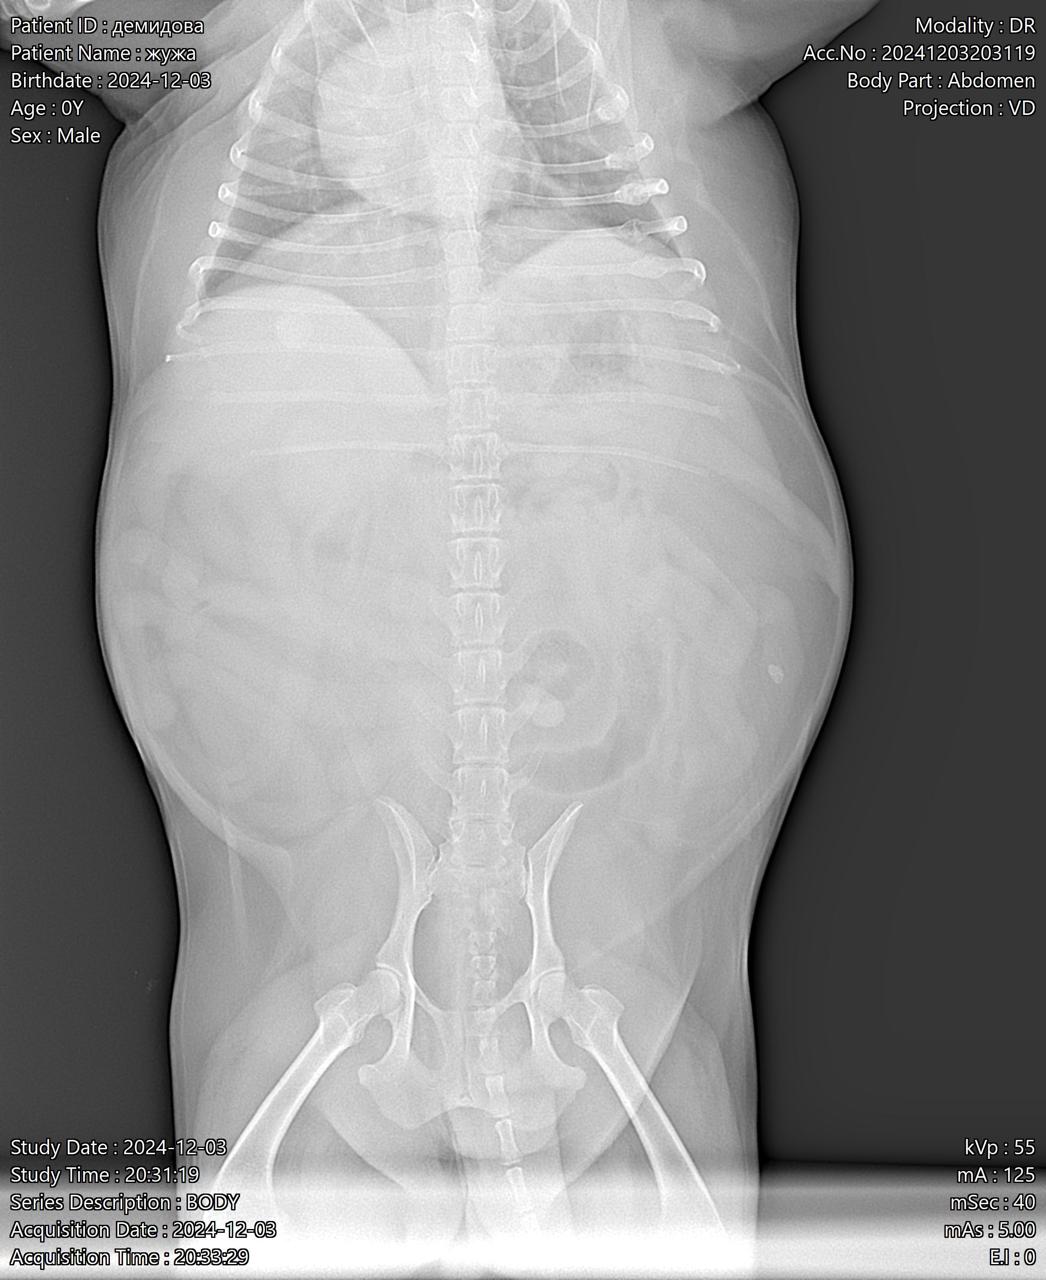

Визит к врачу с поносом

Вложения

IMG-20241203-WA0044.jpg

IMG-20241203-WA0042.jpg

IMG-20241203-WA0041.jpg